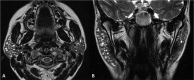

Inflammatory and obstructive disorders of the salivary glands are caused by very different pathological conditions affecting the gland tissue and/or the excretory system. The clinical setting is essential to address the appropriate diagnostic imaging work-up. According to history and physical examination, four main clinical scenarios can be recognised: (1) acute generalised swelling of major salivary glands; (2) acute swelling of a single major salivary gland; (3) chronic generalised swelling of major salivary glands, associated or not with "dry mouth"; (4) chronic or prolonged swelling of a single major salivary gland. The algorithm for imaging salivary glands depends on the scenario with which the patient presents to the clinician. Imaging is essential to confirm clinical diagnosis, define the extent of the disease and identify complications. Imaging techniques include ultrasound (US), computed tomography (CT) and magnetic resonance (MR) with MR sialography.